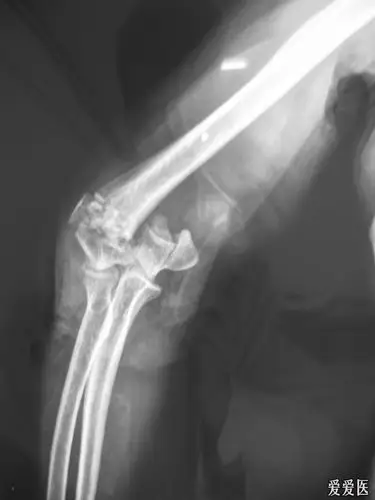

老年肱骨髁间粉碎性骨折 (原创)

辅助检查:x线,ct 临床诊断:左肱骨髁间骨折(iii型) 治疗经过:外院转